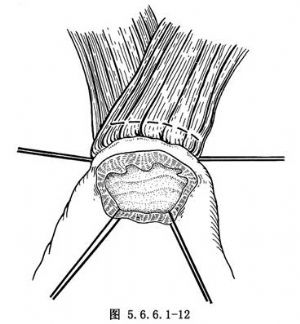

(4)常规食管胃端侧吻合:①先在预计切断食管的平面上方1cm处由食管边缘两侧分别用丝线穿过肌层与黏膜下层,与胃底部预计切开处的浆肌层缝合,两针之间的距离为食管的宽度(图5.6.6.1-10),图中食管壁上的虚线为准备切断食管的平面;②在两根缝线之间加缝数针,将食管后壁与胃底部浆肌层完全缝合(图5.6.6.1-11),图中胃壁上虚线为准备切开胃壁的部位;③切开胃壁浆肌层,但勿切透黏膜,将循行于黏膜下的每根血管用细丝线缝扎两处,然后在缝扎线之间切开胃黏膜。黏膜上切口开始不宜太大,在吻合过程中如嫌不足可再次切开(图5.6.6.1-12)。在切开胃壁之前应先用干纱垫置于吻合口后方以吸取切开胃黏膜后逸出的胃液,切开胃黏膜后迅速将吸引器头送入胃中吸净胃液;④沿预计切断食管的平面环绕食管切开肌层但勿切开黏膜,在食管肌层断面远侧约0.8cm的平面剪断食管黏膜,因留有足够的黏膜,吻合时十分便利,否则如在同一平面切断食管肌层及黏膜,由于后者的回缩使吻合操作相当困难;⑤将吻合口后壁食管全层的左右侧两角分别与胃壁切口的上缘全层用细丝线间断缝合,注意食管黏膜与胃黏膜必须对齐,缝线之间的间隔约为0.4cm,缝线结扎不能太紧以免术后局部组织水肿造成切割,成为发生吻合口瘘的主要因素(图5.6.6.1-13)。结扎线结打在腔内(图5.6.6.1-14);⑥将胃管经吻合口送入胃中,如果应用十二指肠饲食管,可在此时将引导饲食管的糖球一并送入胃中(图5.6.6.1-15),开始吻合前壁。由后壁转往前壁时,两侧转角处的缝线必须缝好,因在转角处容易发生瘘。吻合的最后4~5针最好先挂上线而不结扎,待全部缝合完毕时一次打结;⑦前壁第一层吻合完成以后,撤除原来置于吻合口后方的干纱布块,参加手术人员用无菌净水冲洗手套,将吻合使用过的器械前端用水洗净,用细丝线间断缝合吻合口前壁第二层,完成食管肌层及黏膜下层与胃底部浆肌层之间的缝合(图5.6.6.1-16);⑧将吻合口周围的胃壁用纱布向吻合口方向推送,结扎吻合口前壁第二层的缝线,使吻合口最后被套入胃壁中(图5.6.6.1-17);⑨将胃内引导十二指肠饲食管的糖球挤过幽门,清点台上敷料(包括纱布及纱垫)无误后,用中号丝线间断缝合膈肌。在胃越过膈肌处缝合不宜过紧,防止术后出现梗阻。将胃轻轻上推然后将胃壁与周围膈肌缝合6~7针,防止腹腔内脏器循此途径进入胸腔。注意不要用丝线将胃壁固定在胸壁上,此种缝线可能造成胃壁穿孔。如术者想采取措施减少吻合口的张力,可在近胃底部的胃大弯侧寻找一个切断大网膜的残结,用缝线穿过固定在纵隔胸膜上,同样可以达到吻合口减张的目的而无胃壁穿孔之虞。由第8肋间腋后线置入闭式引流管,检查胸内有无出血点或异物存留。用肋骨合并器将切口上下方的肋骨合拢,肋间组织用中号丝线缝合,冲洗胸壁肌肉,逐层关胸。将闭式引流管连接于水封瓶上。